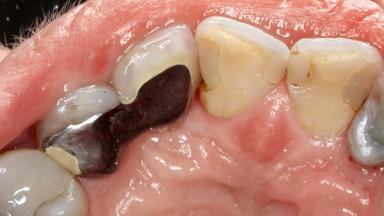

A 65-year-old female patient was referred to the periodontist for assessment and management of infection associated with an implant at site 12. The general dentist had noted suppuration on probing during examination.